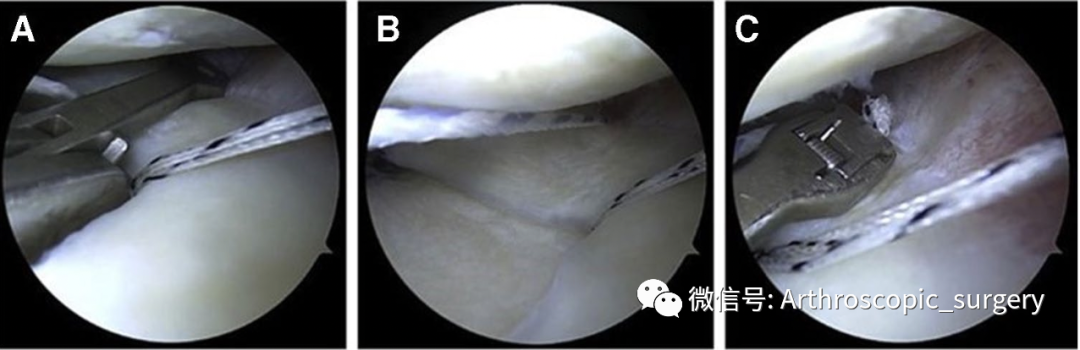

A.新鲜化胫骨平台 (从内侧入路进行观察);B.导向器放置于胫骨平台边缘(中1/2),铆钉间距1cm左右;C.植入铆钉,将缝线从内侧辅助入路取出

A.从外侧入口放置半月板缝合器,将半月板-关节囊交界处进行缝合;B.通过前外侧入路取出缝线;C.再次缝合半月板边缘与关节囊